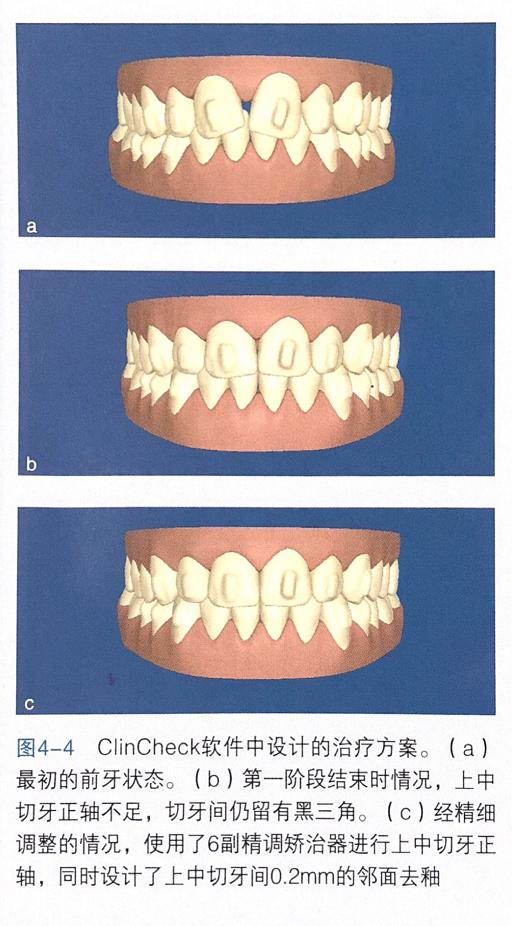

ClinCheck软件中的治疗方案

治疗前首先需要去除维持黑三角的上颌腭侧固定保持丝。治疗最初步骤之一就是正轴。为了上中切牙的正轴,两颗牙上必须使用附件(图4-2),同时近中面需要进行邻面去釉( Interpro×imalename| reduction,|PR)以使接触点往龈方移动。如果同时两颗切牙均处于扭转状态,那么需要在 Clin Check治疗方案中提出,在移动牙冠的最初就开始正轴。有了这种额外的根正轴运动,黑三角就不会进一步恶化。

另外,中切牙近中面的邻面去釉使接触点往根方移动,也会防止黑三角的发生发展。去除上颌腭侧固定保持丝,开始隐形矫治(图4-3)。附件类型为传统矩形附件,因治疗开始时尚未有G4代附件,了防止黑三角,整个治疗过程必须将两颗牙压根靠在一起。